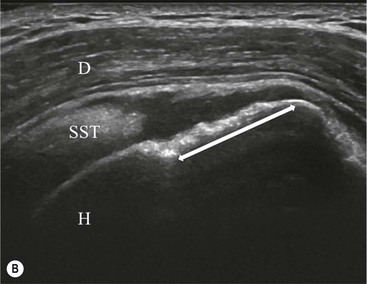

The primary sign of a rotator cuff FTT is a focal deficiency of the tendon (Figs. 46-4 and 46-5). This nearly always occurs at the tendon insertion on the tuberosity. The margins of the tear are best delineated when there is fluid within the tendon defect. Secondary signs of an FTT include the presence of fluid in both the GHJ and SAB, and flattening or concavity of the subacromial fat plane.

PTTs are less reliably demonstrated by both MRI and US, and it may be difficult to differentiate tendinopathy from partial tears. Focal clefts, tears, or tendon thinning affecting the articular margin of the footprint of the tuberosity are most common (Figs. 46-6 and 46-7). Tendon thickening is not always present. It is important not to mistake magic angle phenomenon on short TE MR sequences or anisotropy on US as evidence of tendinopathy.2